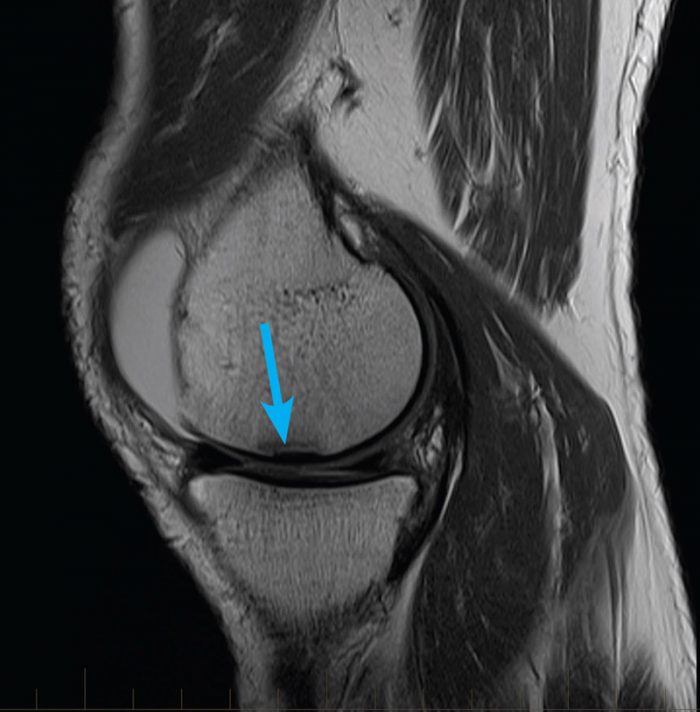

From www.mri.melbourne

mrikneemeniscustear MRI at Melbourne Radiology Clinic Is Running Good For Meniscus Tear Usually, a runner may tear a meniscus when they experience a sudden knee twist, e.g., trip or step on a stone. Causes for meniscus tears from running. The meniscus is vital for distributing weight and providing stability during activities like running. Injury to the meniscus can compromise its ability to distribute load when running, leaving the knee more vulnerable to. Is Running Good For Meniscus Tear.